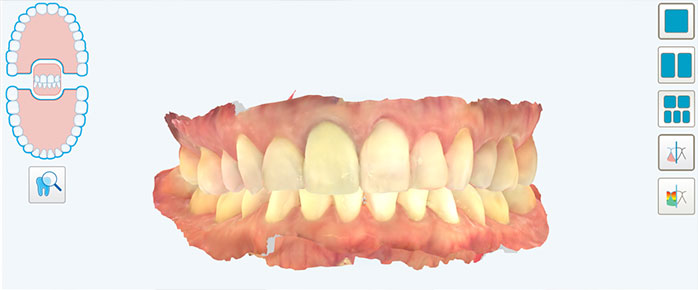

Recursos como escaneamento intraoral, tomografia (CBCT) e escaneamento facial permitem uma avaliação tridimensional completa.

Planejamento digital estratégico, não apenas automático

O ClinCheck, que é o software de planejamento do Invisalign, é uma ferramenta poderosa. No entanto, ele não substitui a experiência do ortodontista.

Em um tratamento de excelência, o ortodontista ajusta cada detalhe: inclinações dentárias, torque, sobrecorreções, sequência de movimentos e uso estratégico de attachments e outros dispositivos auxiliares.

Esse refinamento faz com que o resultado planejado seja mais próximo do resultado real, reduzindo a necessidade de correções posteriores.